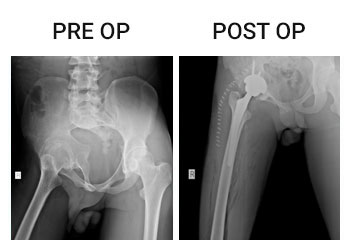

Knee and Hip replacements surgeries are routinely done in this hospital under different categories and Packages. Joint replacement team is headed by Dr.P.Elangovan M.S, Mch Ortho, who has more than 1000 joint replacement surgeries to his credit and is a vastly experienced surgeon and uses both European and American implants. Staggered bilateral knee replacement is the standard practice in this hospital.

• Total Hip Replacement

• Total Knee Replacement